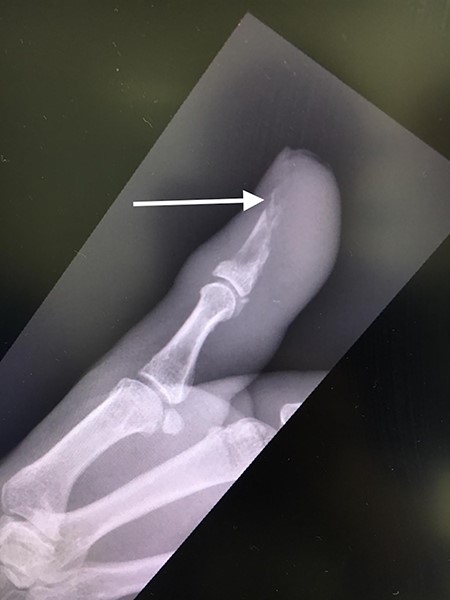

Her blood tests on presentation were unremarkable and X-rays of her right thumb showed a lytic lesion involving the tuft of the distal phalanx (Figs. 4 and 5). She was admitted to the hospital and was treated as having an infection of her right thumb with elevation and intravenous antibiotics. She underwent emergency surgery the next day for a washout and debridement of the right thumb. During the debridement in theatre, there was no pus in the pulp, but the bone was found to be eroded and soft, thus multiple specimens from the bone were sent for microscopy, culture and sensitivity, acid-fast bacilli (AFB) and histopathology.

Lateral X-ray of right thumb showing erosion of tip of distal phalanx and soft tissue swelling.